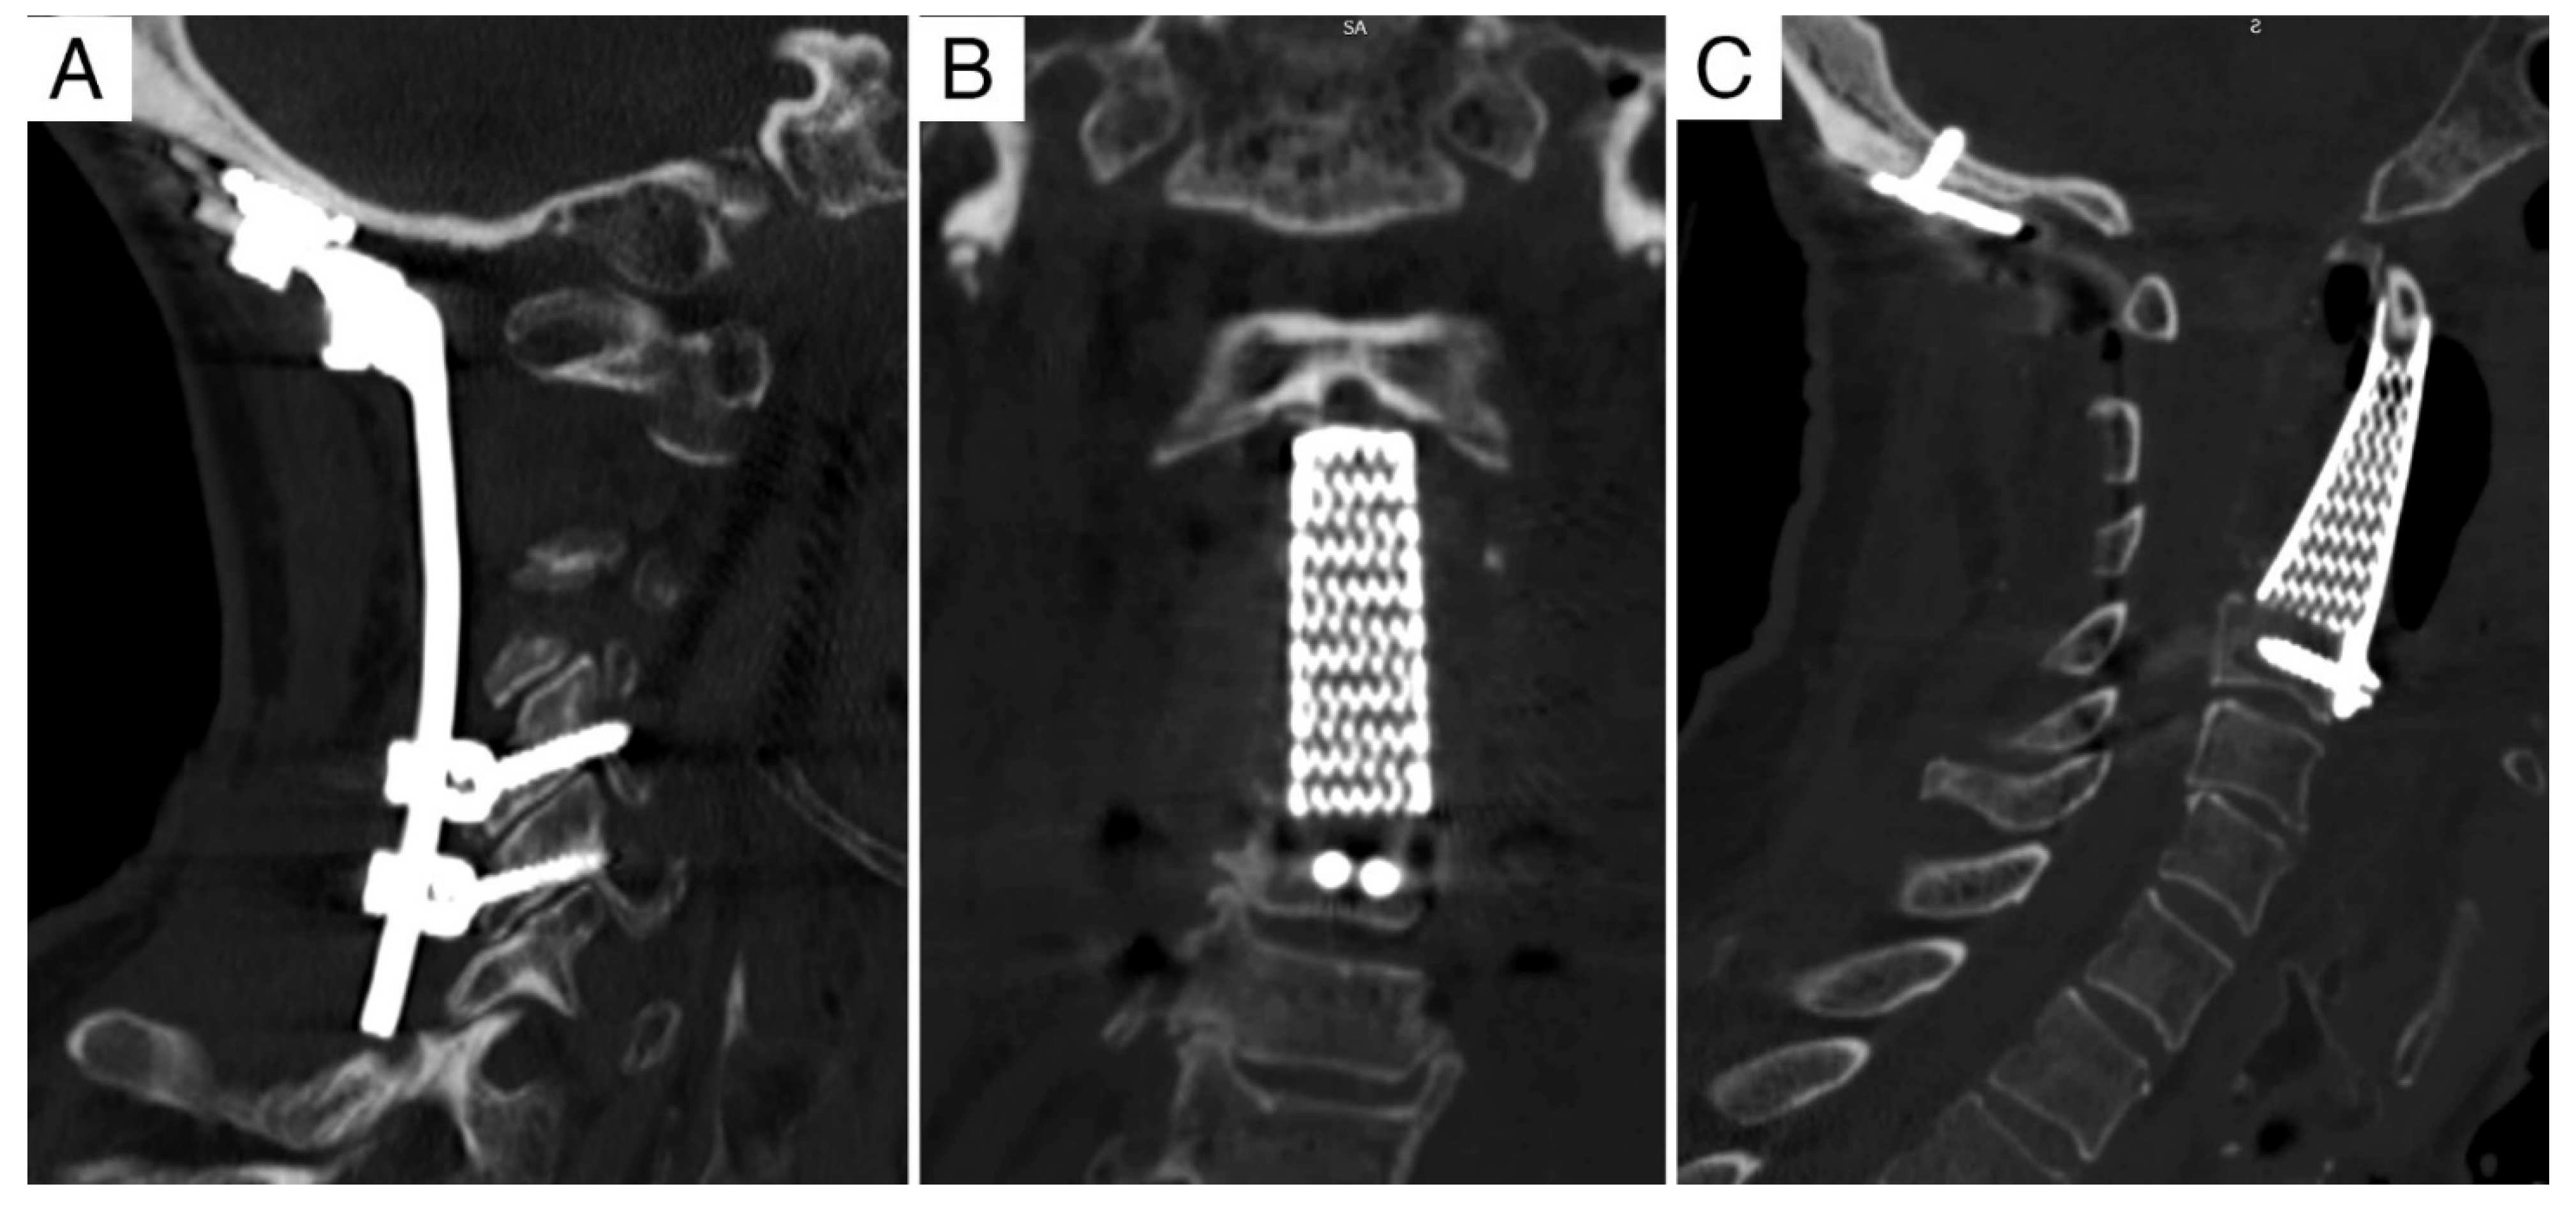

3.3. Reconstruction

| 1 | 65, M | Recurrent chordoma C2 | IB | 8-5/A-D | RT (70.4 Gy carbon-ion, Δt = 4 y) Extracapsular debulking and reconstruction w/ allograft and carbon-fiber buttress plate (Δt = 2 y) | A | Intralesional | 18 | 20 | DOC |

| 2 | 75, M | Recurrent chordoma C2 | IB | 8-3/A-D | Extracapsular debulking (Δt = 8 m) RT (74 Gy proton-ion, Δt = 2 m) | A+P | Intralesional | 12 | 32 | DOD |